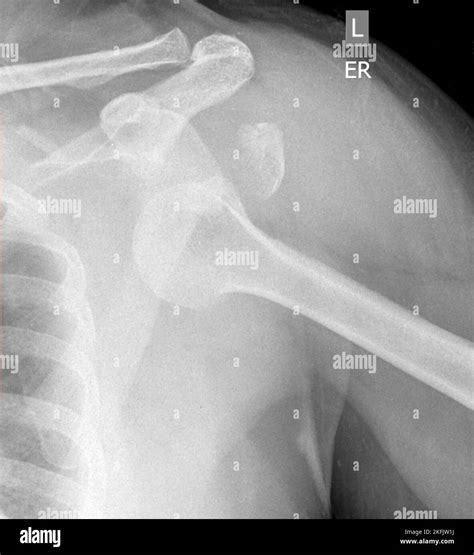

Diagnosis of Inferior Shoulder Dislocation

Diagnosing an inferior shoulder dislocation involves a combination of physical examination and imaging tests. The diagnostic process typically includes:

• Physical examination: A healthcare provider will assess the shoulder for deformity, swelling, and range of motion.

• X-rays: Imaging tests can confirm the dislocation and rule out fractures or other injuries.

• CT scan or MRI: These advanced imaging techniques may be used to evaluate the extent of the injury and plan treatment.

Accurate diagnosis is crucial for determining the appropriate course of treatment and ensuring a successful recovery.